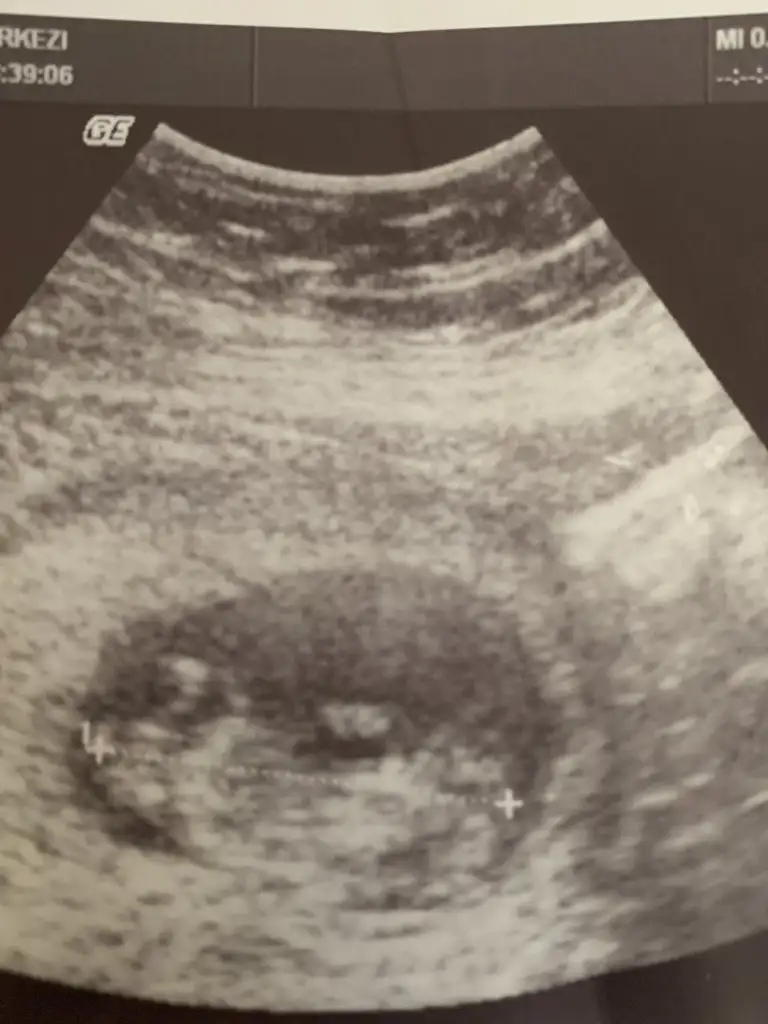

prenses gibiMerhaba benimkinide bakabilirmisiniz 3.hamileleik 7.0 hafta karından

sanki prenses gibiMerhabaPasha22 bana da yorum yapabilir misin biri 6+1 diğeri 8+1 karından